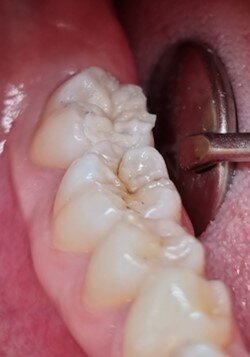

Observation of the lesions showed that the enamel of tooth #47 looked greyish, suggestive of an underlying dentine lesion in need of treatment. The occlusal surfaces were practically intact, without cavitation. Therefore, it was possible to make a copy of the anatomy using a ball instrument and a low-viscosity resin material. In this case, a blue-coloured utility resin (LC Block-Out Resin, Ultradent Products) with good visibility and flow was used, but any resinous material with sufficient flow and strength will do the trick.

First, a thin layer of the resin was applied to the pits and fissures and polymerised (Fig. 2a). A medium-sized ball instrument was then placed on the occlusal surface already covered with the resin and a second layer of resin was added, enclosing the ball. The addition of layers was continued until both the surface and the instrument were sufficiently covered (Figs. 2b & c). The stamp was then separated from the tooth (Fig. 3).

Figs. 2a–c: The anatomy of the occlusal surface was copied with utility resin to create a stamp. The tip of a ball-shaped instrument was incorporated to give a handle to the stamp.

Fig. 3: The stamp shows a detailed imprint of the occlusal anatomy.